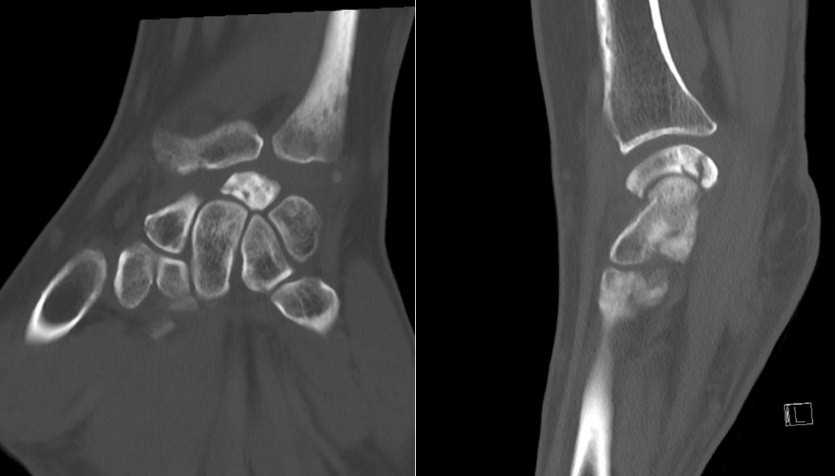

Here, we present two cases of Kienböck’s disease classified as Lichtman stage IIIc, characterized by complete osteonecrosis and a coronal fracture of the lunate, without associated cartilage damage. Both patients underwent a medial closing wedge osteotomy of the radius combined with compression screw fixation of the lunate fracture. The two patients were female, aged 42 and 47 years, with a history of wrist pain. Pre-operative imaging included standard wrist radiography, which revealed a negative ulnar variance (radiographic ulnar index), computed tomography (CT) confirming the presence of a lunate fracture, and MRI demonstrating osteonecrosis (showing a hypointense signal on T1-weighted sequences and a hyperintense signal on T2-weighted sequences, with no gadolinium enhancement). No signs of carpal instability or cartilage degeneration were observed in the surrounding structures.

- Patient A: A 42-year-old right-handed housewife presented with significant pain and stiffness in her dominant wrist persisting for 4 months. She had no history of trauma and was a non-smoker. Her medical history was notable for diabetes and a prior episode of deep vein thrombosis in the lower limb several years earlier (Fig. 1, 2, 3).

Figure 2: Computed tomography scan.

Figure 3: Magnetic resonance imaging.

Figure 5: Computed tomography scan.

Figure 6: Magnetic resonance imaging.